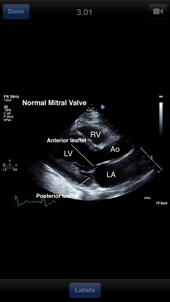

View examples of normal and abnormal echocardiograms with the Echocardiography Atlas. Access 250 annotated images and 189 videos, encompassing a wide range of cardiac pathology. Zoom and pan echocardiograms, and search for specific diseases, without the need for a network connection.

This app serves as an introductory learning tool for students or a comprehensive visual reference for cardiologists, cardiac surgeons, internists, other physicians, and sonographers.